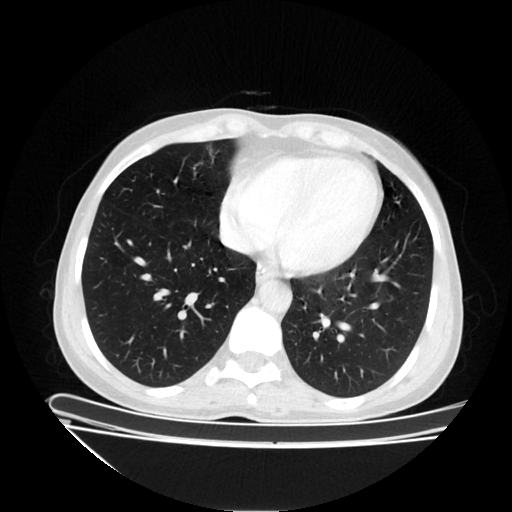

Original NATIVE CT scan (input)

Lung window (WL -600, WW 1500 β†’ Low βˆ’1350, High +150)

Reconstructed NATIVE CT scan (cycle consistency)

Original VENOUS CT scan

Generated VENOUS CT scan (A→B translation)